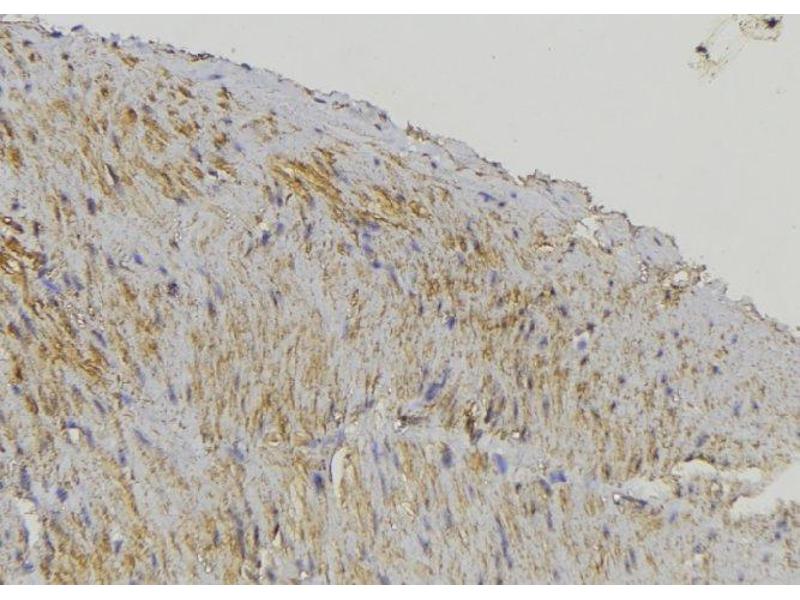

CYP17A1 Reactivité: Humain, Souris, Rat WB, ELISA, IHC, IF, ICC Hôte: Lapin Polyclonal unconjugated

N° du produit ABIN6258050

525,71 €

Plus frais de livraison 40,00 € et TVA

100 μL (Autres quantités disponibles)

Destination: France

Envoi sous 9 à 11 jours ouvrables

CYP17A1 Reactivité: Humain, Souris, Rat WB, IHC, IF, IP, IC Hôte: Lapin Polyclonal unconjugated

N° du produit ABIN7295468

330,77 €

Envoi sous 17 à 20 jours ouvrables